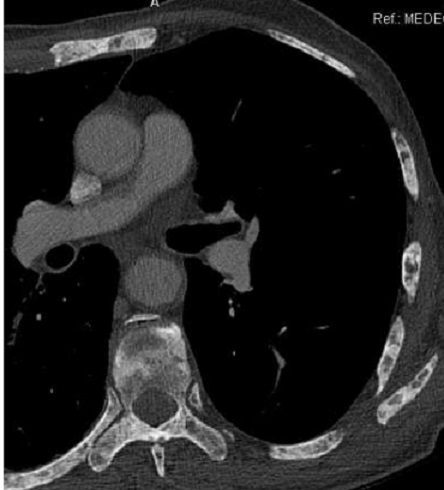

Aspect radiologique de tumeur

metastatique secondaire de type mixte ( lysis et

condensant) multiple disseminé à des côtes du thorax

et à la colonne vertebrale . Image radiologique TDM

en coupe axial , fenêtre mediastinale |